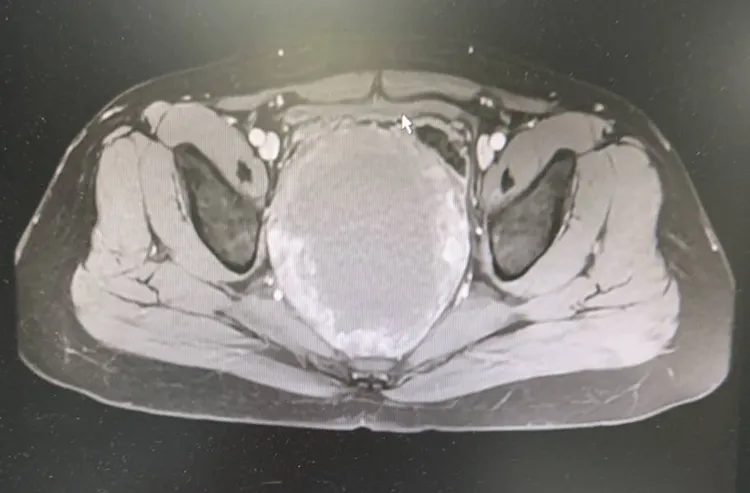

趙先生斷層檢查可見腫瘤位置及大小。阮綜合提供